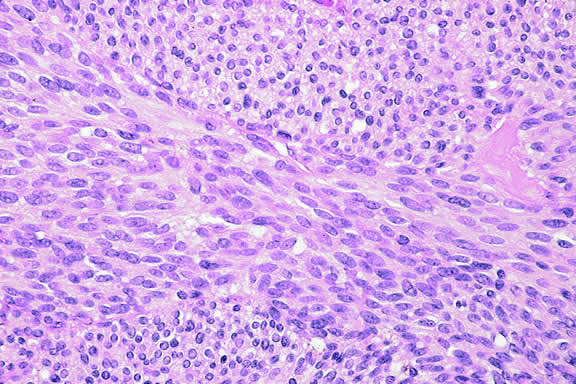

Histopathology

The cells comprising uveal melanoma constitute a biologic spectrum comprising bland spindle A melanoma cells at one end and wildly anaplastic epithelioid cells at the other. The term spindle cell is derived from the fusiform or spindled configuration of the cells' cytoplasmic outline. They are bipolar in shape, and many have long tapering processes that occasionally are highlighted when individual pigmented cells are seen in a largely amelanotic tumor. Spindle cells grow in a syncytial fashion forming interweaving fascicles of parallel oriented cells (Fig. 30). The cells can be pigmented or nonpigmented. Two types of spindle cells are recognized; spindle A and spindle B. These are distinguished by their nuclear characteristics. Spindle A nuclei are tapering ovals or cigar-shaped and have finely dispersed chromatin (Fig. 31). If a nucleolus is present, it usually is inconspicuous. Many spindle A cells have a longitudinally oriented chromatin stripe that actually is caused by a fold in the nuclear membrane. The nuclei of spindle B cells have distinct nucleoli and coarser chromatin and tend to be plumper and more oval in shape (Fig. 32).

Fig. 30. Amelanotic spindle cell melanoma. Tumor is composed of interweaving fascicles of spindle cells. Photomicrograph shows longitudinally and transversely sectioned fascicles. (Hematoxylin-eosin, × 100.)

Fig. 31. Low-grade spindle melanoma. Spindle A cells have bland, slender, cigar-shaped nuclei with finely dispersed chromatin and indistinct nucleoli. Longitudinal folds in the nuclear membrane are apparent microscopically as a chromatin stripe or line. Bland spindle B nuclei with distinct nucleoli also are present. (Hematoxylin-eosin, × 250.)

Fig. 32. Spindle B melanoma cells. Most of the cells in this field are spindle B melanoma cells. They have oval nuclei and an obvious nucleolus. Compared with spindle A cells, their chromatin is more coarsely clumped. The spindle cells form a syncytium and have indistinct cytoplasmic margins. (Hematoxylin-eosin, × 250.)